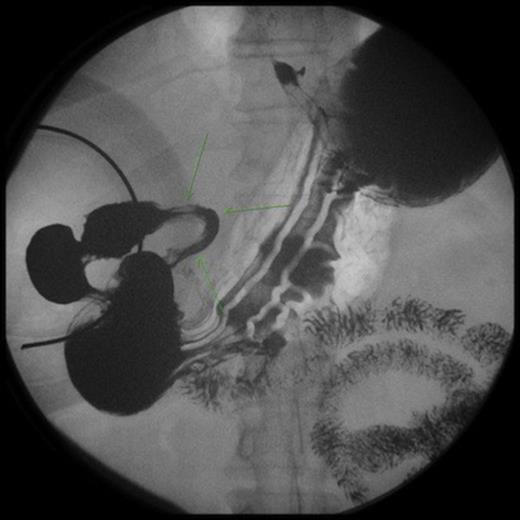

An upper endoscopy showed distal tertiary esophageal contractions, small sliding hiatal hernia with mild gastroesophageal reflux, and an intestinal obstruction at the level of the second portion of the duodenum. The mucosa was normal with the lumen completely constricted. A CT scan demonstrated distension of the stomach and first portion of the duodenum. An UGI study showed severe stenosis of the second portion of the duodenum.

An exploratory laparotomy demonstrated an olive type mass in the second portion of the duodenum involving a 5 cm segment of the second portion of the duodenum with thickening of the duodenal wall measuring up to 1.3 cm. A longitudinal duodenotomy showed a diverticulum at the ampulla and two biopsies of the wall were taken. The incision was closed longitudinally and a gastrojejunostomy was performed.